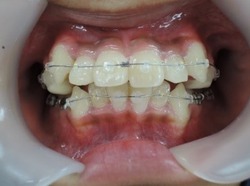

以下の上顎の症例では左右の第一小臼歯を抜かないと治療出来ないと説明があるはずです。しかし、当院での治療終了時には顎骨が拡大して綺麗に歯が並んでいます。

初診時 終了時

治療期間3年0か月で機能的で美しい咬み合わせが完成しました。

今回の症例は一般的に抜歯(第一小臼歯)が必要な症例ですが当院では非抜歯で治療する事が出来ました。